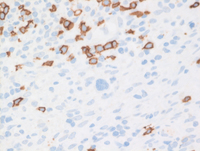

CD20 and PAX5 downregulation in cHL

CD20 immunostain (bottom left) demonstrates scattered small B cells staining positive for CD20 while the Hodgkin cells are negative for CD20, consistent with down regulation of germinal center and B-cell program in the cells.

Likewise, PAX5 (bottom right) demonstrates strong nuclear positivity in the surrounding B cells while the clusters of the Hodgkin cells in the center of the field demonstrate weak PAX5 expression consistent with the down-regulation of germinal center and B-cell program in these cells.